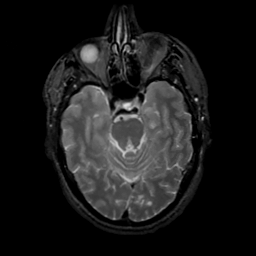

MR Study #13, May 19, 1991 -- Slice #17